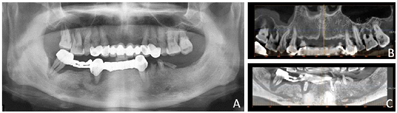

患者口腔卫生差,14、13、12、11、21、22、23、24固定(桥)修复体松动Ⅰ度,边缘不密合,16、17、26根面暴露,Ⅲ度松动,叩诊(±),27缺失。33、32、31、41、42、43、44、45、46、47固定(桥)修复体Ⅱ度松动,边缘不密合,34、35、36残根,断面平龈缘,37缺失。下前牙舌侧结石(+),牙龈红肿,上下颌余留牙牙龈退缩(图1)。

(2)2015年9月行拔牙及上颌种植手术。口腔局部阿替卡因肾上腺素注射液浸润麻醉,拔除上下颌余留牙,搔刮清理拔牙窝内肉芽组织,见43、44、47区牙槽骨缺损(图4),修整下颌牙槽嵴,黏膜瓣复位,4-0可吸收缝线缝合下颌术区。16~26区牙槽嵴顶近远中向切开牙龈黏膜、翻瓣,平整牙槽嵴顶骨嵴,分别于12、15、22、25区定点,逐级备洞,15区倾斜植入Nobel Speedy 4 mm×15 mm种植体,12、22、25区骨质量较差,为获得良好初期稳定性选用Nobel Active种植体,12区植入Nobel Active 5 mm×13 mm种植体,22区植入Nobel Active 4.3 mm×13.0 mm种植体,25区倾斜植入Nobel Active 5 mm×13 mm种植体,种植体初期稳定性均达到35 N·cm,旋入复合基台,修整牙龈,缝合。术后拍摄全颌曲面体层片(图5)。